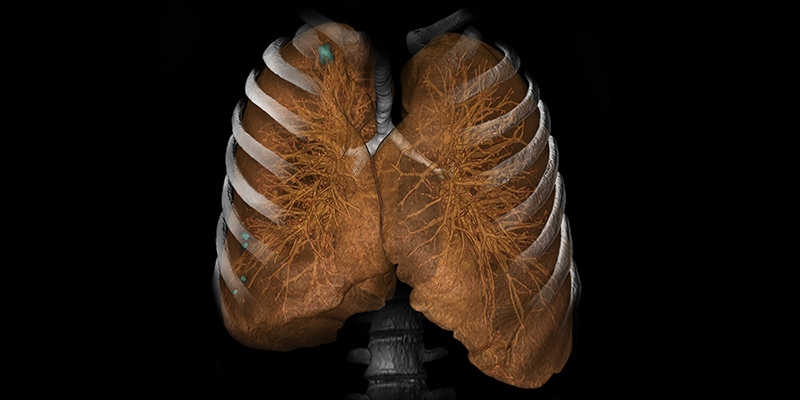

КЛІНІЧНІ ЗАСТОСУВАННЯ

ІНФОРМАЦІЙНИХ ТЕХНОЛОГІЙ VITREA